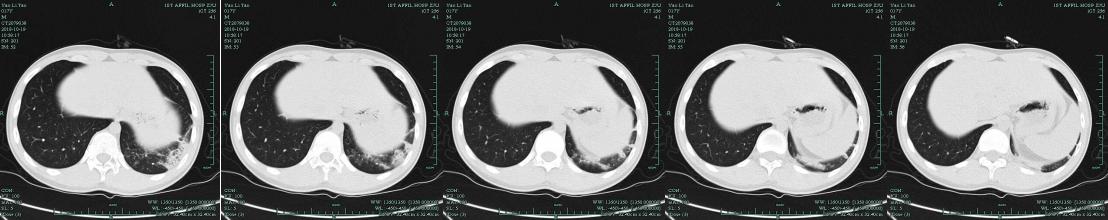

入院后肺部CT提示双肺弥漫性病变。这个病人是不是重症社区获得性肺炎?

/入院后肺部CT/